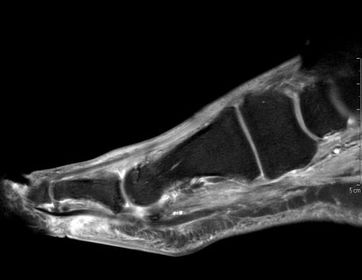

| What does this indicate? | Increased signal and enhancement of the soft tissue plantar to the proximal phalanx suggestive of subcutaneous infection without abscess |

| What does this indicate? | Increased signal and soft tissue distension dorsally representing subcutaneous abscess communicating with associated with plantar ulcerative defect. |